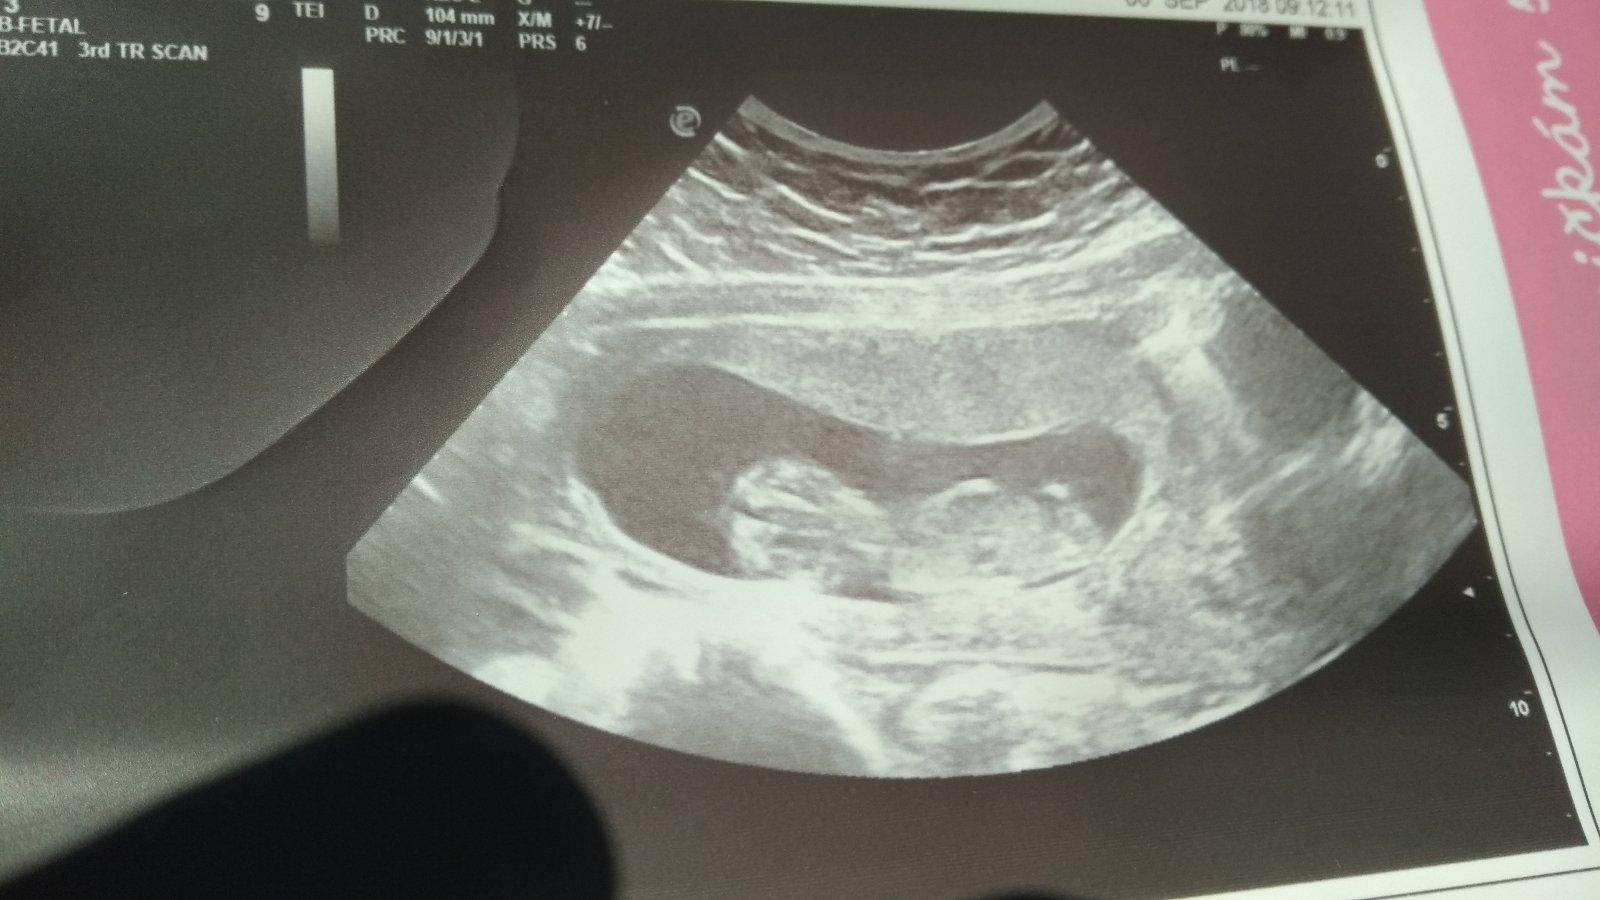

Caute zienky. Tak ja som doma z kontroly. Nas drobcek poriadne vyrastol, uz sme s manzelom videli aj nozicky, aj rucicky (aj prstiky na ruke😍), ako si tam nadskakoval. Bolo to uzasne! O tyzden idem na krv, tak budem mat zase trosku stres, len sa modlim, aby bol zdravucky❤️❤️❤️ Pekny dnik vam prajem!

A termin stale drzime 31.3.:)